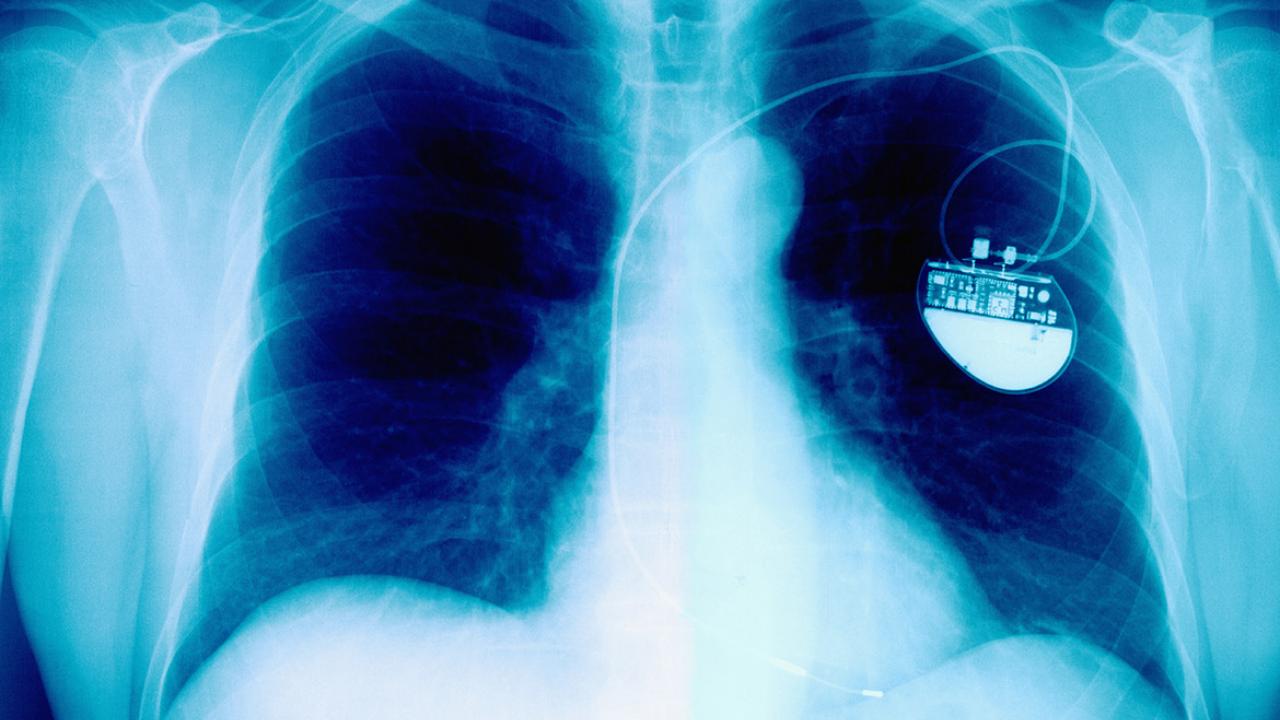

Some one in 10 Americans will have a medical device implanted into their bodies at some point in their lifetimes, yet less than 1% of these devices have been tested in rigorous clinical trials regarded as standard by U.S. regulators.

The September issue of AMA Journal of Ethics® (@JournalofEthics) explores implantable material and device regulation, particularly the tension inherent in clinician-investigators’ and the FDA’s obligation to balance patient-subjects’ safety with patients’ demand for timely access to technologies and interventions that might improve or extend their lives.